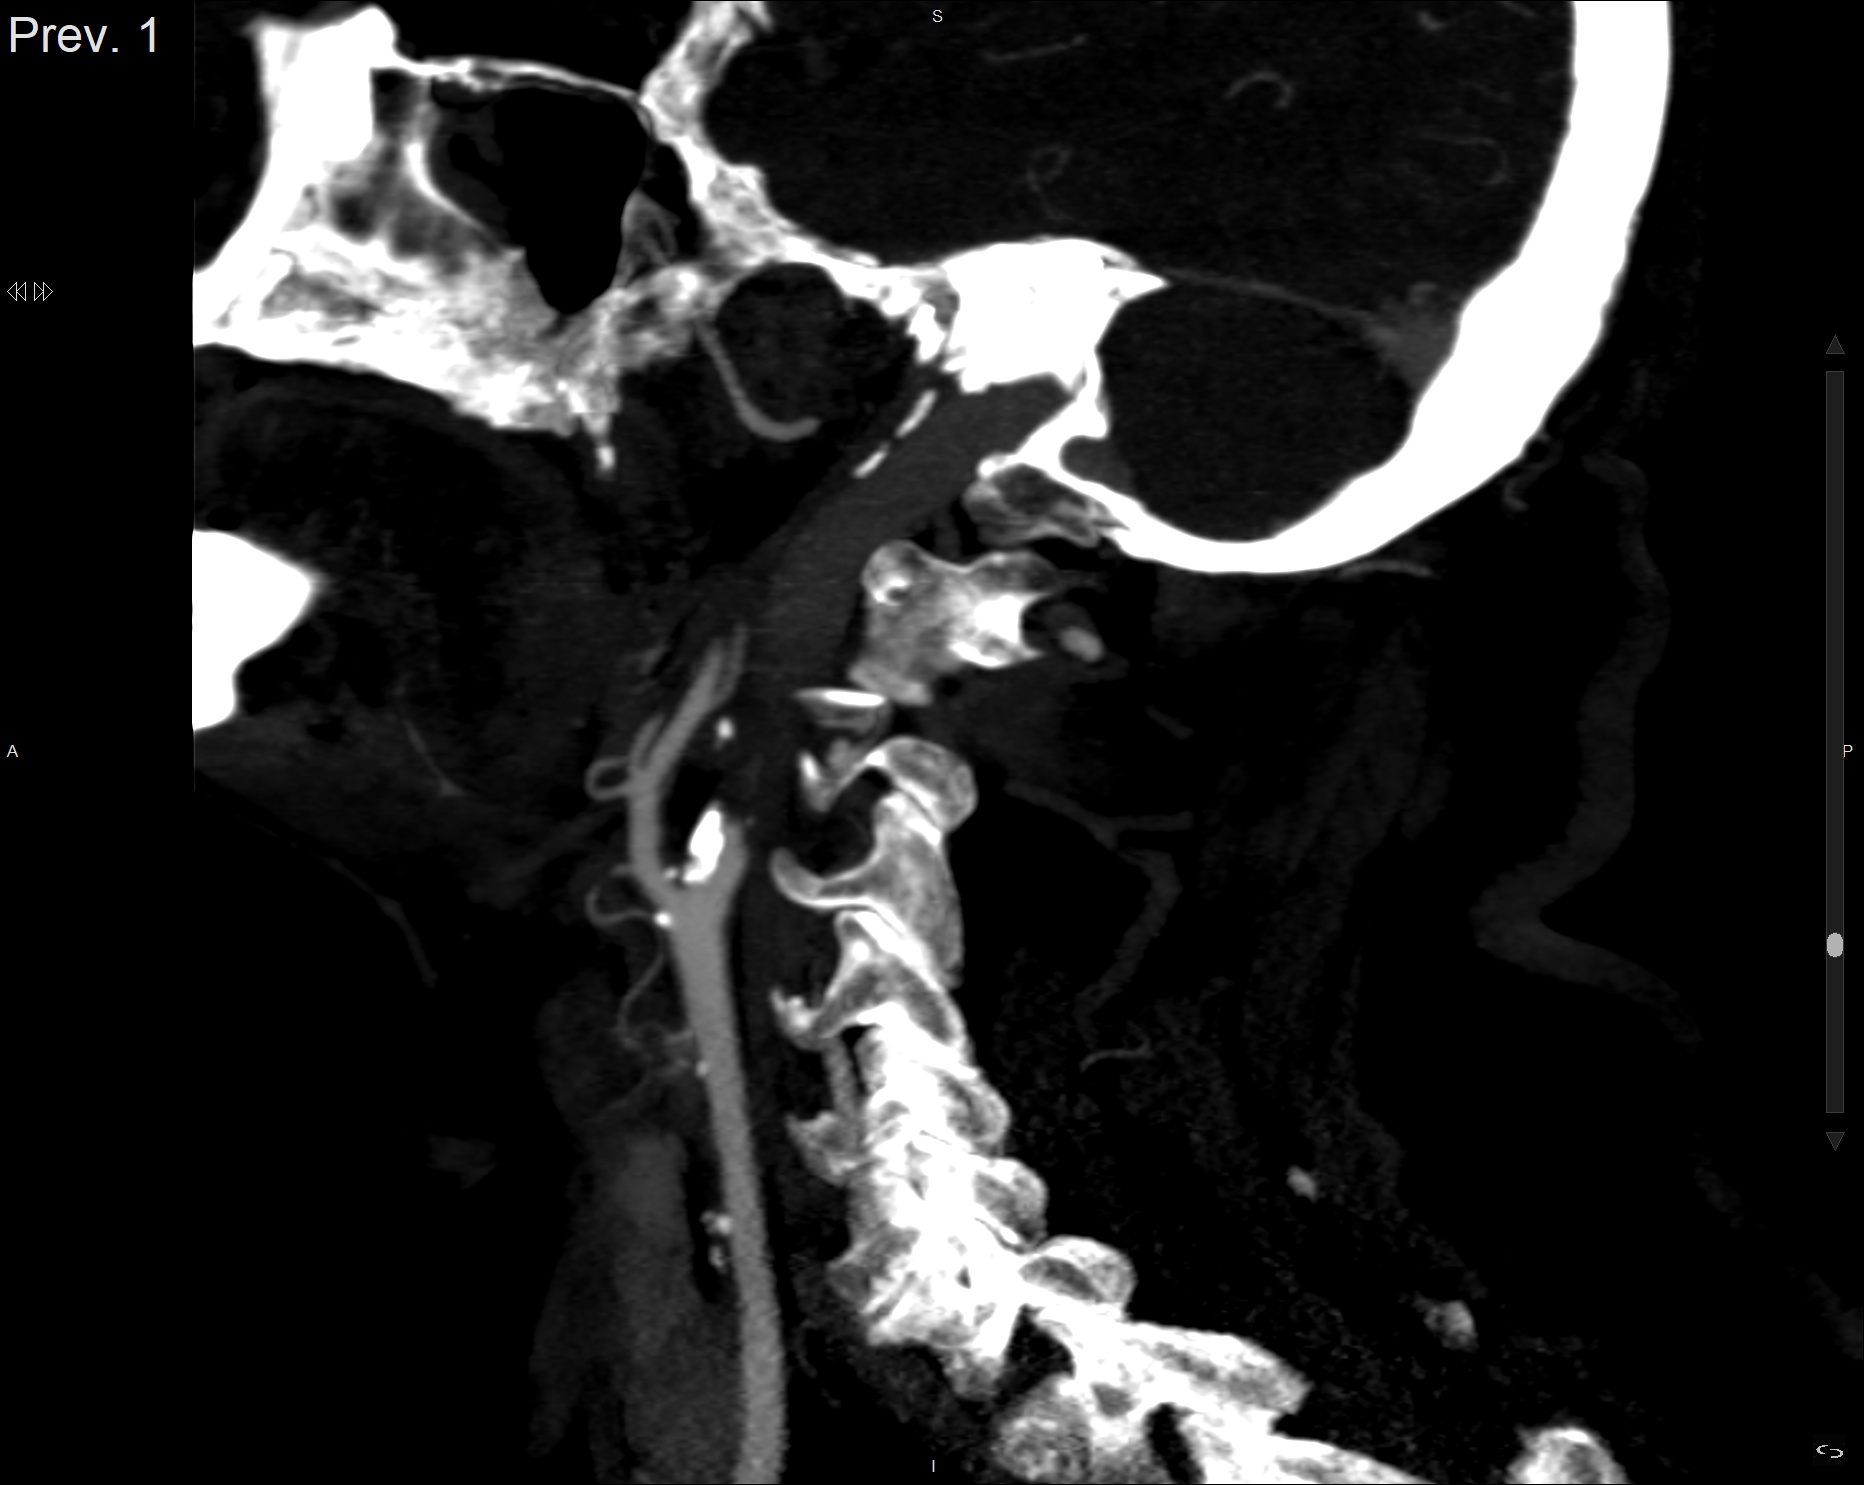

ANGIO-TC EXTRA E INTRACRANEAL:

Aorta y segmentos proximales de troncos supraaórticos permeables con signos de ateromatosis no estenosante. Origen y segmentos cervicales de ambas arterias carótidas internas con ateromatosis, causando una oclusión total de la derecha y una estenosis >80-90% de la izquierda. Origen y segmentos cervicales de las arterias vertebrales permeables con signos de ateromatosis no estenosante.

Segmentos intracavernoso y supraclinoideo de las arteria carotida interna derecha ocluido (no visible).

Segmentos intracavernoso y supraclinoideo de las arteria carotida interna izquierda ocluido (no visible).

Segmento M1 de la ACM izquierda con defecto de repleción ocupando su luz, presentando una

repermeabilización distal. Oclusion de la A2 izquierda con repermeabilizacion distal. Resto de las principales arterias cerebrales intracraneales (ACM derecha, ACPs, Basilar, V4s) permeables